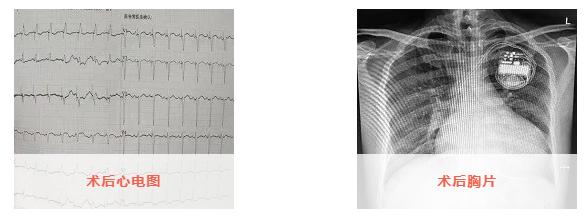

已完成心脏再同步化治疗的这两名患者均为心功能IV级、心脏左室射血分数不足30%(其中一名患者EF为14%,左室舒张期内径达88mm)存在完全性左束支传导阻滞,虽经最佳药物治疗心功能仍持续恶化。在科室副主任尹波的指导下,经过充分术前风险评估及手术准备,由毕方杰博士完成这两例LOT-CRTD,现患者均已顺利出院。其中,患者孙某术前完全不能下床活动,术后患者已恢复日常活动。出院半个月随访,患者心衰症状明显缓解,活动耐量较术前显著增加,6分钟步行试验已由术前0米提高至452米左右,术后短期内达到了对心脏再同步化治疗的超反应。